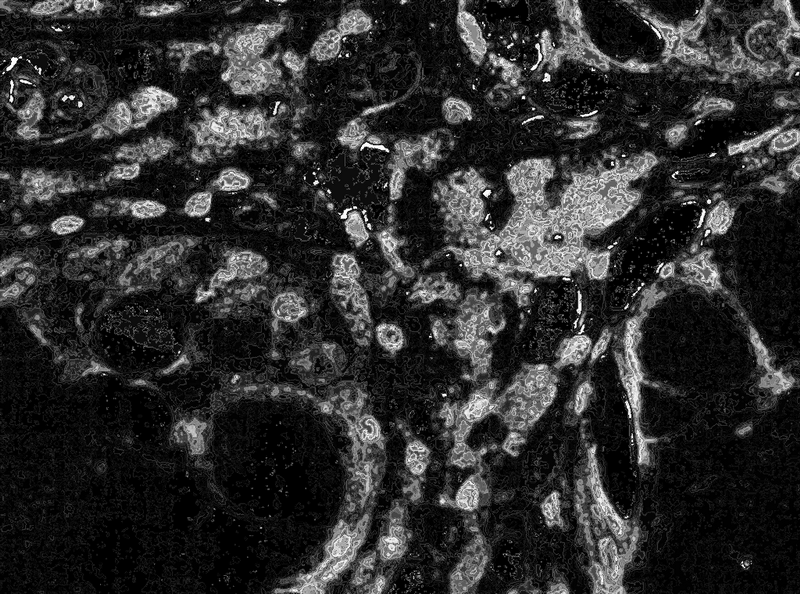

Морфометрическое исследование осуществлялось с помощью системы компьютерного анализа микроскопических изображений, состоящей из микроскопа Leica DMR, цифровой камеры Leica DC300, персонального компьютера на базе Intel core i3 и программы Leica QWin. В каждом случае анализировалось 5 полей зрения при увеличении × 400, определялась относительная площадь экспрессии сигнальных молекул (см. рис. 1), которая представляет собой отношение площади, занимаемой иммунопозитивными клетками, к общей площади клеток в поле зрения, выражаемое в процентах. При статистической обработке использовали T-критерий Фишера – Стьюдента (Statistica 9, StatSoft).

Рис. 1. Экспрессия FasL (иммуногистохимический анализ, Diagnostic BioSystems, 1 : 75) в одном поле зрения препарата слизистой толстой кишки (× 400)